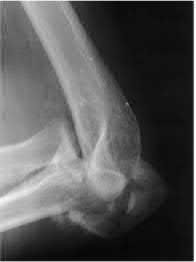

A 12-year-old male sustains an ulnar fracture with an associated posterior-lateral radial head dislocation. After undergoing closed reduction, the radiocapitellar joint is noted to remain non-concentric. What is the most likely finding?

In pediatric Monteggia fractures the annular ligament is commonly interposed in the radiocapitellar joint.

Bado initially described and classified Monteggia fractures. The most common injury pattern is an extension type 1 with anterior radial head dislocation and apex anterior ulnar shaft fracture. The apex of the ulna fracture determines the direction of the radial head subluxation or dislocation. Adults typically require ORIF of the ulna. These fractures in children are often treated non-operatively with closed reduction if the ulna fracture is transverse and stable. Type III is the one most commonly associated with irreducibility of the radial head because of interposition of the annular ligament. The incidence of posterior interosseous nerve injury is high with this lesion. The nerve deficit usually completely resolves rapidly and spontaneously.

Tan et al reviewed their treatment of 35 children with Type I and Type III Monteggia fractures. All radial heads were explored and the interposed annular ligament was stretched out of the joint space. They noted that none of the patients had any recurrent dislocation or subluxation.

Ring et al in their review stress the importance of an anatomic reduction of the ulna to restore the reduction of the radial head.